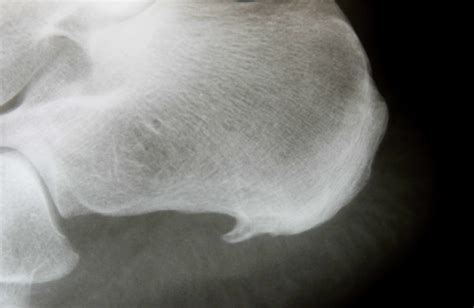

Diagnosing heel spurs typically involves a combination of physical examination and imaging tests. A healthcare provider will assess the foot for tenderness, swelling, and range of motion. Imaging tests such as X-rays, ultrasound, or magnetic resonance imaging (MRI) may be used to confirm the presence of a heel spur and rule out other potential causes of heel pain.